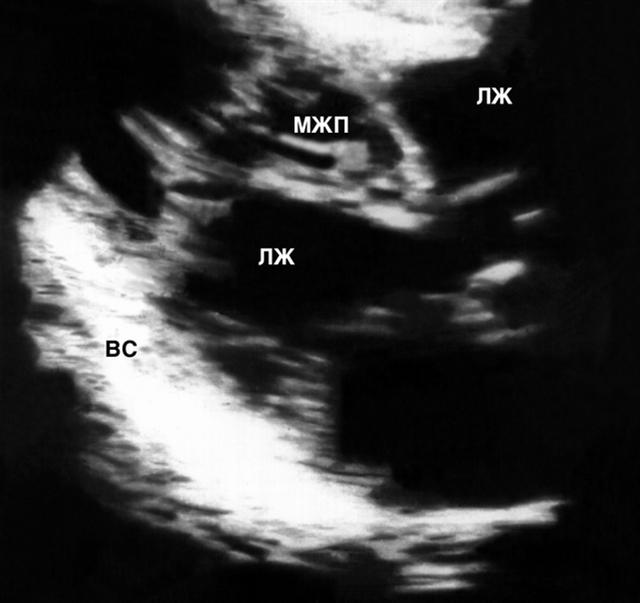

Рис. 5а). Двухмерная эхокардиограмма при верхушечной кардиомиопатии: ПЖ — правый желудочек, МЖП — межжелудочковая перегородка, ЛЖ — левый желудочек, ВС — верхушка сердца. Видно значительное нарастание толщины миокарда левого желудочка в направлении от основания к верхушке сердца.